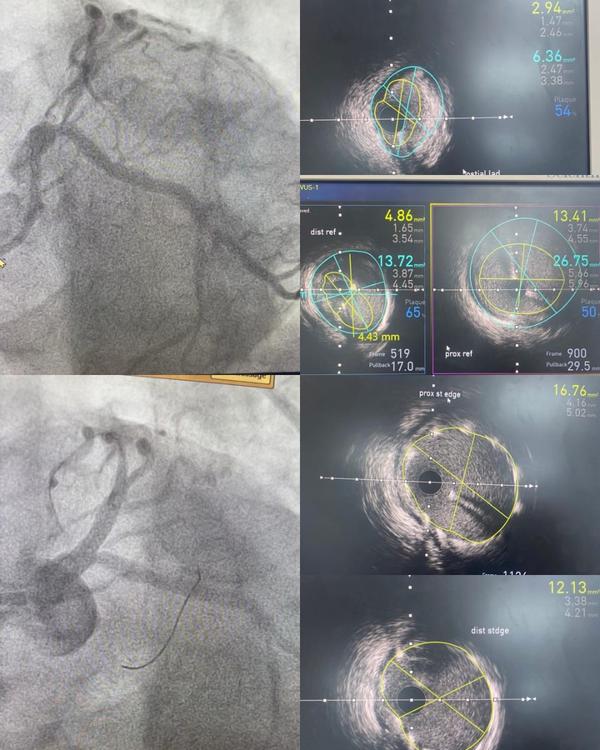

Angioplasty and Stent Placement Angioplasty and stent placement is a minimally invasive, image-guided procedure used to treat coronary artery disease (CAD) — a condition caused by the narrowing or blockage of the heart's blood vessels due to plaque buildup. What is Angioplasty? Angioplasty, also known as Percutaneous Coronary Intervention (PCI), involves the insertion of a small balloon through a catheter into a narrowed coronary artery. The balloon is gently inflated to widen the artery and restore blood flow to the heart muscle. What is a Stent? In most cases, a stent — a small, mesh-like metallic scaffold — is placed at the site of the blockage to keep the artery open permanently. Drug-eluting stents are commonly used to reduce the risk of re-narrowing (restenosis). When is it recommended? Acute heart attack (STEMI/NSTEMI) Unstable angina or chest pain not relieved by medication Significant coronary artery narrowing found on angiography High-risk coronary lesions with compromised blood flow Benefits of Angioplasty and Stenting Rapid symptom relief (e.g., chest pain, breathlessness) Minimally invasive with faster recovery Improved heart function and reduced risk of heart attacks Short hospital stay (typically 1–2 days) Advanced Techniques Available For patients with complex or calcified lesions, we also offer: Rotational Atherectomy (ROTA) Intravascular Lithotripsy (IVL) Intravascular Ultrasound (IVUS) CHIP angioplasty for high-risk cases

CHIP Angioplasty

Image Gallery

Pictures That Speak

Complex Angioplasty in Nashik